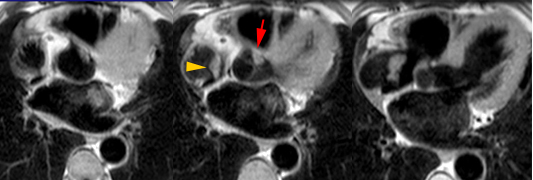

– Les abcès annulaires infectieux ou froids calcifiés constituent de bonnes indications pour l’IRM cardiaque.

– L’IRM est un complément intéressant dans les suspicions de fibroélastomes (mais moins performant que l’ETO).